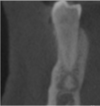

What is the radiographical finding?

Odontogenic

Keratocyst

OKC

Is this Globulomaxillary Cyst , lateral granuloma or OKC?

~ it is kind of a teardrop or pear shaped size

~Little less well differentiated in this particular instance but again unilocular radiolucency between the roots of two teeth

This one ended up being an OKC